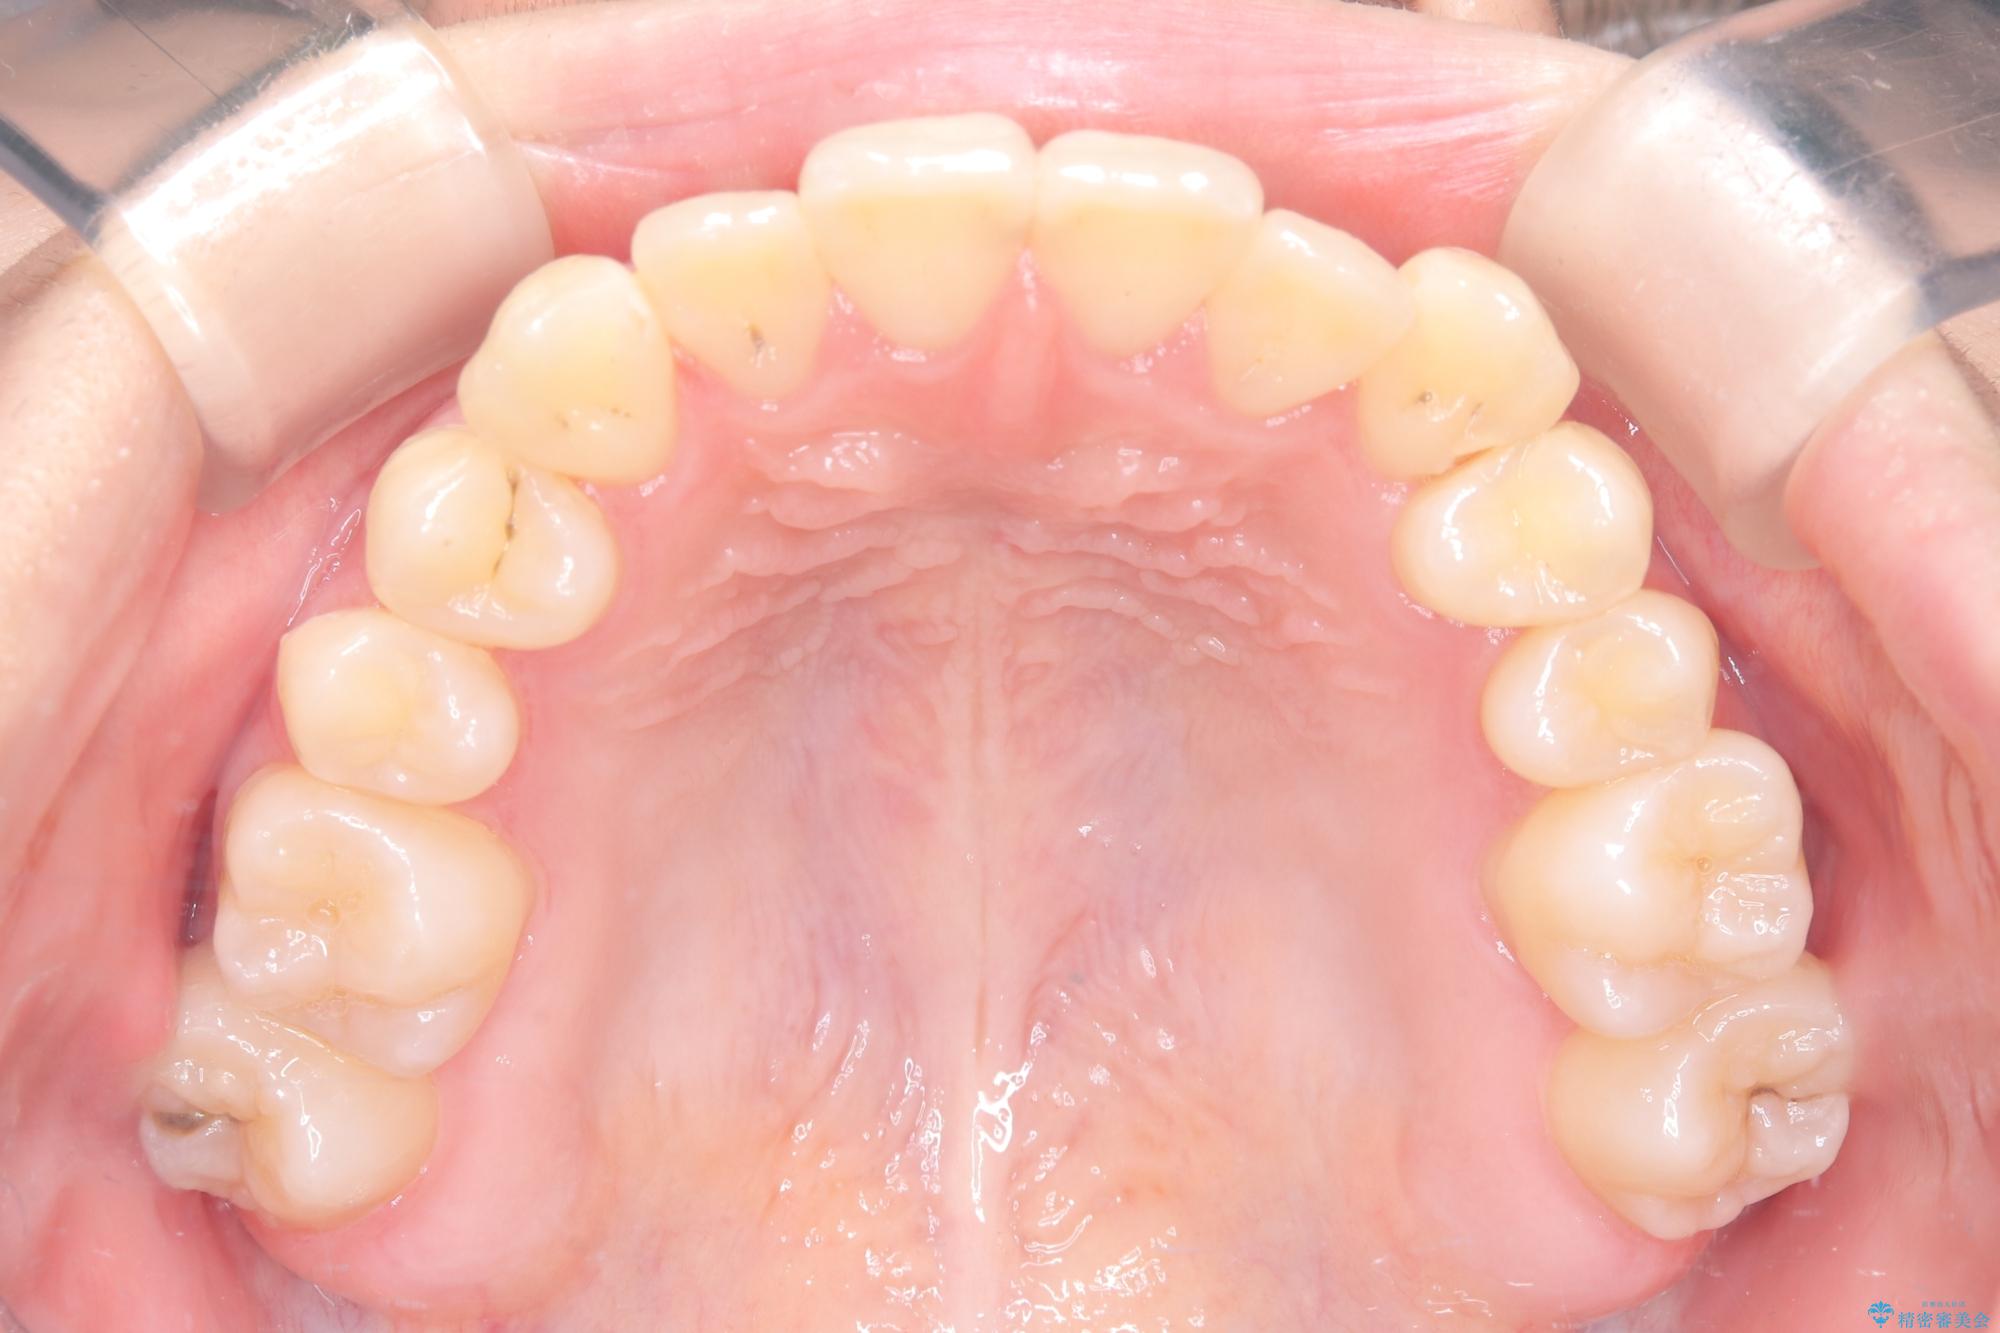

安全かつ確実に抜歯スペースを閉じ、咬み合わせを完成させるため、マウスピースから**ワイヤー矯正(マルチブラケット装置)**へ切り替えるリカバリープランを提案しました。

装置の変更と歯肉への配慮: ワイヤー矯正は歯の根(歯根)を平行に移動させる「歯体移動」を得意としています。本症例では、歯肉退縮を防ぐために、歯の傾きを精密にコントロールしながら抜歯スペースを閉じる必要がありました。ワイヤー装置を用いることで、インビザラインでは難しくなっていた三次元的な細かい調整を可能にしました。